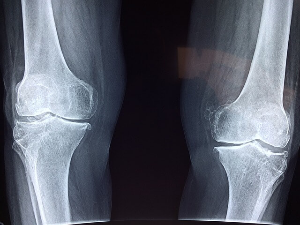

치료와 운동

골다공증 치료는 뼈의 손실을 늦추거나 중단시키고 골절의 위험을 줄이고 전반적인 뼈 건강을 개선하는 것을 목표로 합니다. 이는 약물치료, 생활습관, 운동의 조합이 있습니다. 약물치료는 뼈 손실을 늦추고 골절 위험을 줄이는데 도움이 되며 골밀도를 유지해 주는 호르몬 치료가 있습니다. 그리고 칼슘과 비타민D는 뼈 건강에 필수적입니다. 칼슘은 유제품, 잎이 많은 채소, 칼슘 강화식품과 보충제에서 얻을 수 있고 비타민D는 피부가 햇빛에 노출되었을 때 몸에서 생성되며 지방이 많은 생선, 계란 노른자를 섭취하면 좋습니다. 평소 균형 잡힌 식사를 하고 흡연과 과도한 알코올 섭치를 피하고 체중 유지 운동을 하는 것은 모두 뼈 건강을 유지하는데 도움 됩니다. 운동을 하게 되면 골밀도, 힘, 균형을 향상해 주며 걷기, 조깅, 춤, 계단 오르기와 같은 체중을 지탱하는 운동은 특히 뼈 건강에 이롭습니다. 역기를 들어 올리거나 저항 밴드를 사용하는 저항 운동 또한 골량을 만들고 유지해 주며 타이치나 요가와 같은 균형 운동은 넘어지거나 골절될 위험을 줄이는데 도움이 됩니다. 안전하고 효과적인 운동 프로그램으로 나만의 운동 루틴을 만드시기 바랍니다.